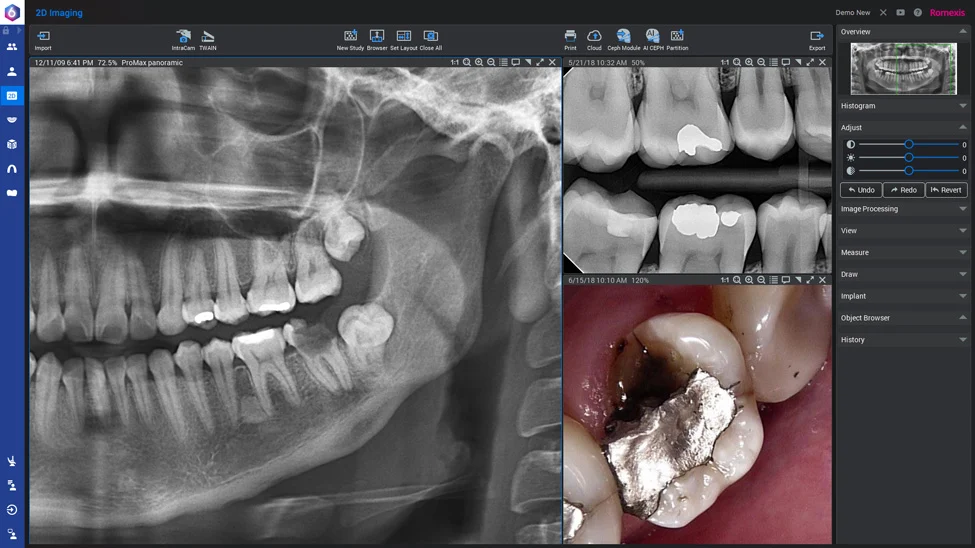

OPG (Dental X-Ray)

Dental X-Ray Dubai at Deira Medical Diagnostic Center: Overview

When it comes to diagnosing dental issues with precision, an Orthopantomogram (OPG), commonly known as a dental X-Ray, plays a pivotal role. This advanced imaging technique provides a comprehensive, panoramic view of your entire mouth, including teeth, jawbones, and surrounding structures, enabling dentists to detect problems such as cavities, impacted teeth, gum disease, or jaw abnormalities with unmatched accuracy.

An OPG, or panoramic dental X-Ray, creates a two-dimensional image of the entire oral cavity.

Unlike traditional X-Rays that only focus on specific areas, an OPG captures a broad view, including:

- Teeth and their nerves

- Upper and lower jawbones

- Temporomandibular joints (TMJ)

- Sinuses

- Surrounding oral structures